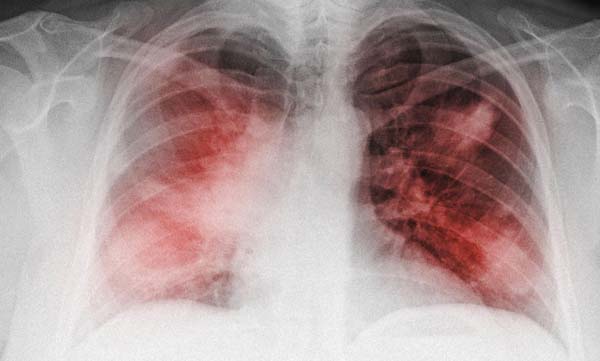

肺炎是发生在肺部的炎症,是比较严重的,肺炎会引起病人严重的咳嗽,甚至气喘,危害病人的身体健康。了解导致肺炎的原因,对症下药,才能更好的治疗肺炎。

大部分肺炎起病急,病程短,病程在一个月以内的为急性肺炎;病程在1~3个月的称为迁延性肺炎;超过3个月的则属慢性肺炎。所以肺炎疾病,及时诊断和治疗很重要。